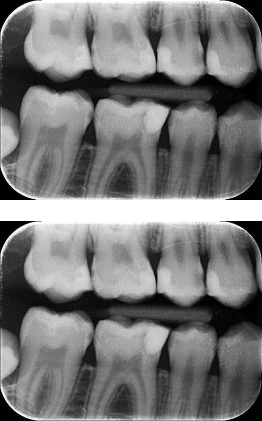

Deze twee kleine röntgenfoto’s worden in overleg gemaakt. Op deze foto kunnen we beoordelen of u gaatjes heeft, oftewel cariës.